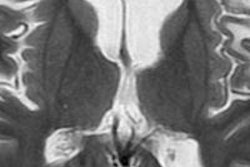

In a study published in Neuron, MR imaging of 25 adult volunteers was used to identify key components in the ventrolateral frontal cortex area of the brain and how these components connect to other brain areas. This part of the brain is involved in many of the highest aspects of cognition and language and is present only in humans and other primates.

Using the MRI data, the researchers divided the human ventrolateral frontal cortex into 12 areas that were consistent across all subjects. These 12 regions could then be compared with the organization of the monkey prefrontal cortex.